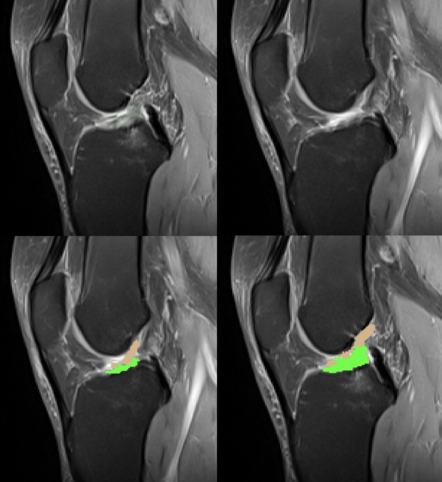

- RMN (rezonanță magnetică nucleară): metoda de referință pentru confirmarea diagnosticului, evidențiind ruptura ligamentului și eventuale leziuni asociate (menisc, cartilaj).

RMN leziune completa LIA